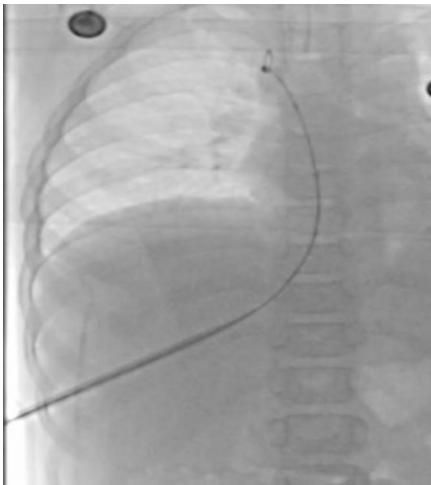

经肝导管置入:如图3所示,经肋间入路穿刺中肝静脉,导管经皮下隧道引出至腋中线。术后X线(图5)需确认导管位置。